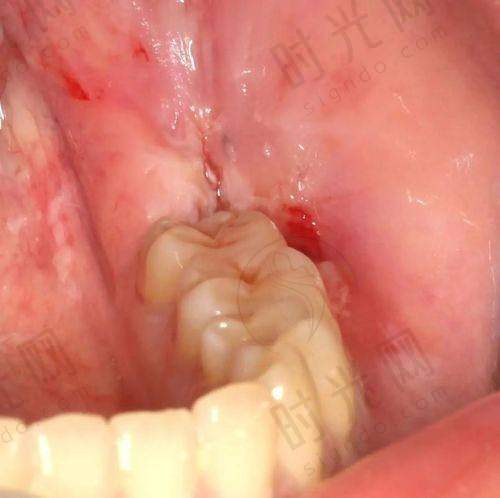

患者情况:23岁大学生,右下智齿横向萌出,露出1/3牙冠,偶尔发炎肿痛,X光片显示牙根直,离神经较远。

技术亮点:STA计算机控制麻醉 + 微创挺子拔除

过程揭秘:医生用STA麻醉仪(针头比头发丝还细,计算机控制推药速度)打麻药,患者几乎没感觉;然后用微创挺子插入智齿与牙龈之间,轻轻旋转挺松,末尾用拔牙钳取出。全程15分钟,出血量不到5ml,术后冰敷2小时,当天就回学校上课了。

患者反馈:“比打疫苗还轻松,后悔没早拔!”